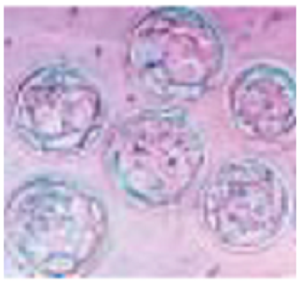

Human cumulus cells attached to the base of the dish growing in the SYNBIOS® SYNTHETIC PROTEIN-FREE EMBRYO CULTURE medium. The synthetic medium can support the growth of human cumulus, granulosa and stem cells. It is likely it may support the development and growth of other cells as well.

Human cumulus cells growing in clumps in the SYNBIOS® SYNTHETIC PROTEIN-FREE EMBRYO CULTURE MEDIUM.